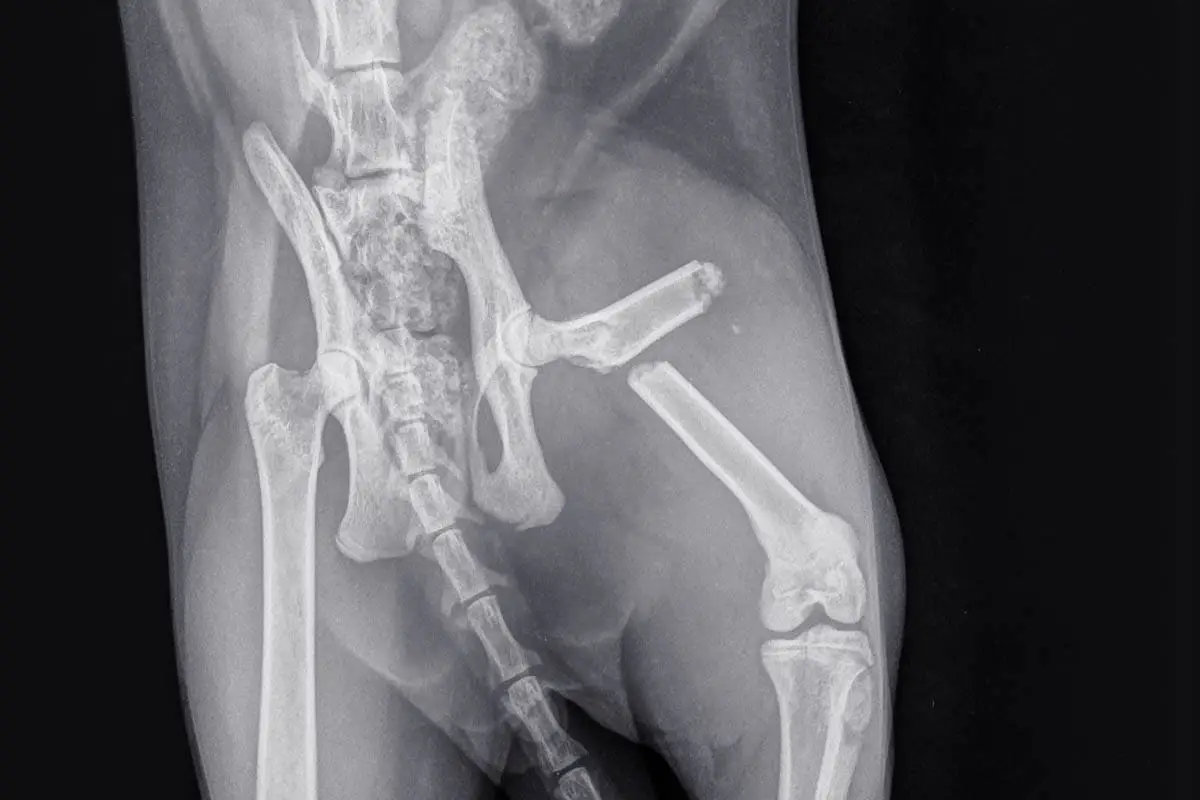

La mayoría de los huesos rotos que afectan a los gatos se deben al trauma, como ser golpeado por un automóvil o una caída en la altura. Otras causas de los huesos de las piernas rotas incluyen infección ósea, cáncer y desequilibrios hormonales que debilitan el hueso.

Las rupturas de huesos más comunes que se ven en los gatos son una pelvis rota, piernas rotas y cola rota. Este artículo se refiere a las piernas rotas, para obtener más información sobre la pelvis rota en los gatos, Leer aquí .

Los gatos con fracturas deberán ser examinados cuidadosamente por su veterinario, ya que pueden tener otras lesiones, como una pelvis rota, órganos de tejidos blandos y daños (por nombrar algunas).

El veterinario realizará una radiografía para verificar la ruptura y evaluar el alcance del daño.

Imagem RJ22, Shutterstock